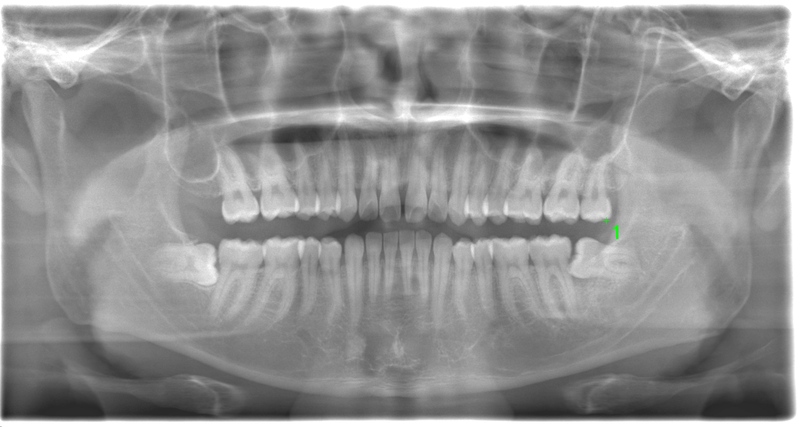

CASE 1

基本情報

| 年齢・性別 | 30代・女性 |

| 主訴 | 左右に分けて親知らずを抜きたい、できれば痛くなく抜きたい |

| 親知らずのはえ方 | 完全に出ていてまっすぐはえている |

| 抜歯期間 | 15分 |

| 抜歯費用 | 約2,000円(保険内) |

| 抜歯内容 |

何度か虫歯になり痛みはないが早めに抜きたい。 完全に頭が出ているため歯ぐきを切ったり骨を削らずに抜歯しました。 根の形も単純なため抜歯自体は5分もかからず上下ともに終わりました。 術後痛みや腫れも出ていません。 抜歯後は感染をしやすいため必ず抗生物質を飲み切ってください。 |